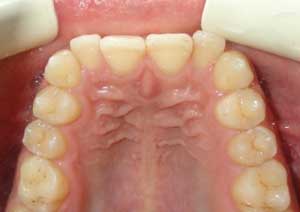

Traitement : Dans ce cas, nous avons eu recours à la mise en place de cales postérieures en résine bleue au niveau des premières molaires maxillaires, Elles ont permis de séparer temporairement les mâchoires afin de laisser les dents du haut se replacer correctement devant celles du bas, corrigeant ainsi le cross-bite antérieur.

Par la suite, ces cales ont été déplacées sur les faces palatines des incisives maxillaires dans le but d’optimiser l’articulé postérieur, notamment au niveau des molaires droites, qui présentaient également un articulé inversé.

Après